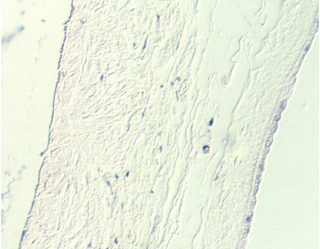

Slide 90 shows uterine epithelium undergoing the decidual reaction. The area is shown in the photos below.  Pieces of placenta might be seen attached to the outer edges.

decidua2.jpg (80318 bytes)decidua3.jpg (60561 bytes)